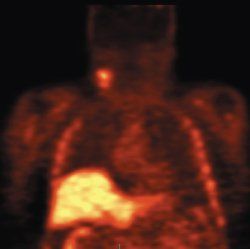

In head and neck cancer, FLT-PET could be used to identify how much marrow has been suppressed after radiotherapy (see Figure). In a study done by Dr. Graham's group at the University of Iowa, the FLT uptake and change early after treatment in squamous head and neck tumors was adequately characterized with SUV obtained at 45 to 60 minutes and correlated well with other post-treatment markers (J Nucl Med 50:1028-1035, 2009).

Top, baseline FLT-PET scan showing radiotracer uptake in right neck nodes and normal distribution of FLT in the bone marrow and liver. Follow-up FLT-PET scan (Bottom and Top Of Article) after 10 Gy of radiotherapy and one cycle of chemotherapy. The uptake in the right neck nodes is decreased. There is also complete disappearance of FLT uptake in the irradiated bone marrow in the cervical spine consistent with marked reduction of cellular proliferation. Images courtesy of Yusuf Menda, MD, and the Universtiy of Iowa department of radiology.